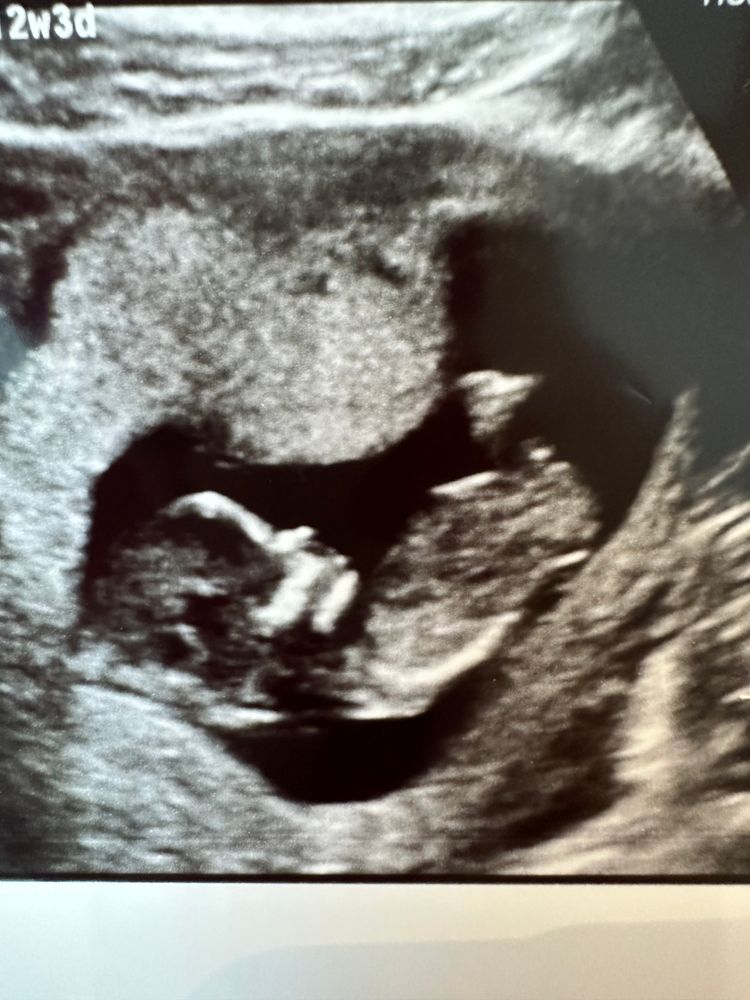

Мама мальчика (3 года), жду мальчика, 16 неделя

Вот и наступил день первого скрининга, на экране картинка казалась очень нечеткой, либо из за того что мочевой пузырь был полон... с сыном на этом сроке картинка была на много чётче😳

как думаете девочка или мальчик?😀

Это нормально, что картинка бывает нечеткой на первом скрининге. Полный мочевой пузырь действительно может влиять на качество изображения. Главное, что все в порядке с малышом.

Да ну, классная картинка)

Пол рано, и не видно